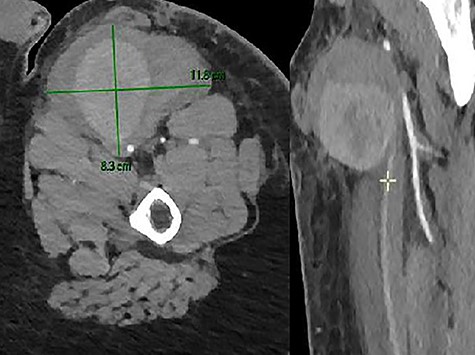

Unfortunately, in the meantime, he presented to the emergency room for a swelling of his left thigh since the morning. He had no pain. He was hemodynamically stable. His hemoglobin was 13 g/dl. We examined a large pulsatile mass of the left upper leg. The CTA showed a PSA (8.3 × 10.7 × 9 cm) of his left SFA and a hematoma with active bleeding on the anterior aspect of the left thigh, in close contact with the left SFA (Fig. 7).

The patient was operated as an emergency. A voluminous hematoma was observed involving muscle tissues in the anteromedial region of the thigh. Proximal control was obtained, the aneurysm incised and the distal control obtained with a fogarty catheter. The hematoma was evacuated and the PSA was resected. The anatomical structures are hardly recognizable and deformed due to the presence of this important hematoma. Our old venous bypass was not visualized, probably compressed and evacuated with the hematoma. The reconstruction performed by interposition of graft (Dacron 6 mm), with end-to-side anastomosis.